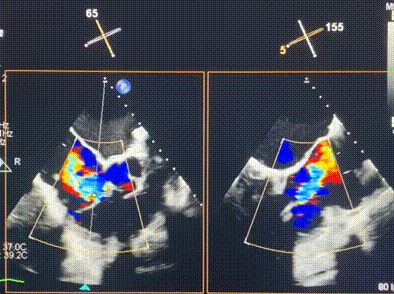

術(shù)前超聲提示重度三尖瓣反流

接受本次LuX-Valve Plus治療的是一位三尖瓣重度反流的高齡女性,患者早前曾由于二尖瓣疾病行經(jīng)導管二尖瓣置換術(shù),植入Tendyne瓣膜一枚,且有ICD植入史。術(shù)前CT分析結(jié)果顯示,瓣環(huán)大小為47.6mm,血管無明顯迂曲和鈣化。由于患者三尖瓣解剖結(jié)構(gòu)復雜,二尖瓣位人工瓣膜造成的超聲偽影和ICD導線的干擾使得歐洲沒有其他合適的商業(yè)化和臨床試驗的產(chǎn)品可以對其進行治療。經(jīng)過Rodrigo Estévez-Loureiro教授團隊的詳盡術(shù)前評估,認為LuX-Valve Plus經(jīng)導管三尖瓣置換系統(tǒng)可以對該患者進行有效的治療。因此,Rodrigo Estévez-Loureiro教授團隊最終決定使用這一中國創(chuàng)新器械為患者進行手術(shù)。法國波爾多里爾大學附屬醫(yī)院的Thomas Modine教授與加拿大圣保羅醫(yī)院的Anson Cheung教授全程線下指導本次手術(shù)。